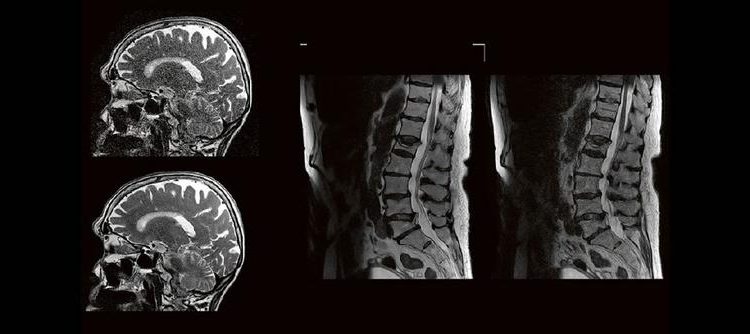

Professor Dr. med. Marc Brockmann WEITERENTWICKLUNGEN VON KOPF BIS FUSS BEIM VC Oberstarzt Dr. med. Stephan Waldeck DEEP-LEARNING-REKONSTRUKTION IN DER NEURORADIOLOGIE Die CT ist ein essentielles Routine-Verfahren in der Neuroradiologie. Bei steigender Bildqualität konnte die Röntgendosis mit neuen Technologien in der letzten Dekade deutlich gesenkt werden, was für die zielgerichtete und möglichst schonende Behandlung von […]

Professor Dr. med. Matthias PumbergerPD Dr. med. Torsten Diekhoff Die Dual-Energy-Computertomographie (DECT) hat für viele klinische Anwendungen bereits Einzug in die Praxis genommen. Für die Behandlung von Wirbelsäulenerkrankungen sind besonders die Darstellung von Knochenmarkveränderungen (z. B. bei osteoporotischen Frakturen) und der Bandscheibe (z. B. bei Bandscheibenvorfällen) interessant und werden intensiv beforscht. Hierdurch versprechen wir uns […]

Jan Hendrik Falkenstein Künstliche Intelligenz spielt in der klinischen Anwendung eine immer größer werdende Rolle. Im radiologischen Sektor erfährt besonders die Magnetresonanztomographie aktuell einen regelrechten KI-Hype. Kürzere Untersuchungszeiten, eine höhere Bildqualität oder eine Kombination aus Zeit und Qualität sind theoretisch möglich, doch ist die KI in der Praxis mehr als eine Spielerei? Wie aufwendig ist […]